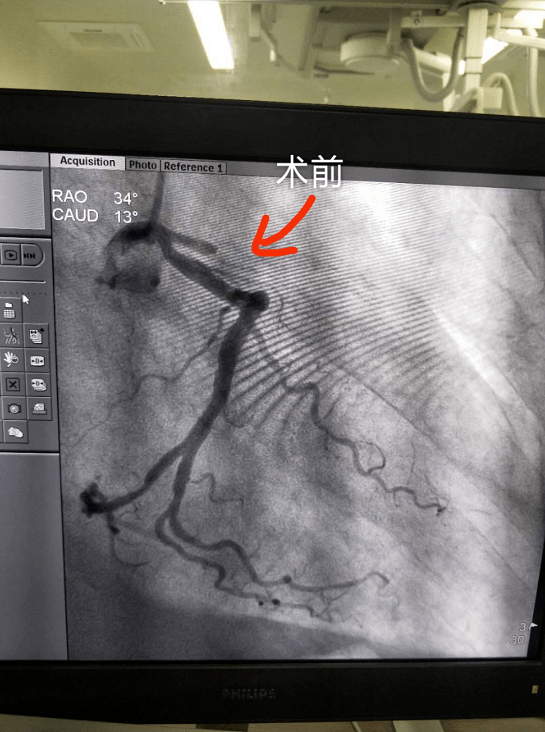

急诊冠脉造影示左前降支近段血栓形成并完全闭塞.